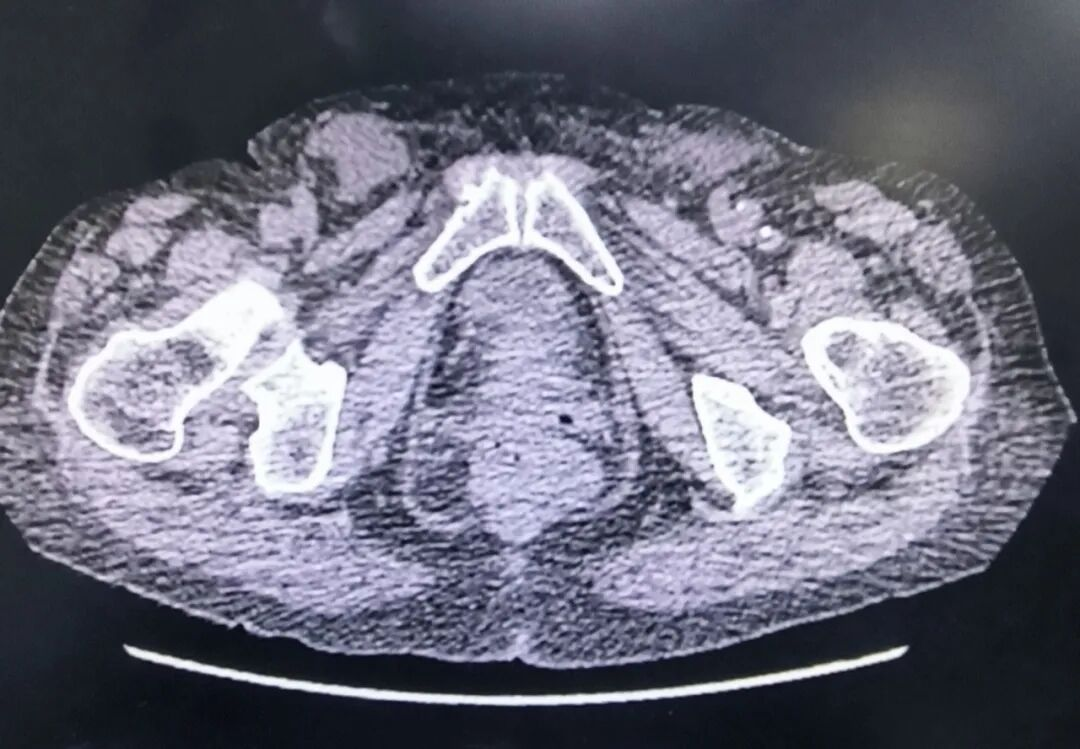

近日,我院普外科顺利为90岁高龄患者实施局麻下无张力双侧疝修补术,解除10余年顽疾,嵌顿疼痛消失,生活质量大幅提升,现已康复出院重获健康生活!

双侧腹股沟疝病史长达10余年,因高龄、基础疾病多,长期忍受疝气带来的不适与行动不便,严重影响日常生活。我院普外团队凭借丰富的临床经验,采用局部麻醉+微创无张力修补技术,最大限度降低手术风险,缩短恢复时间。